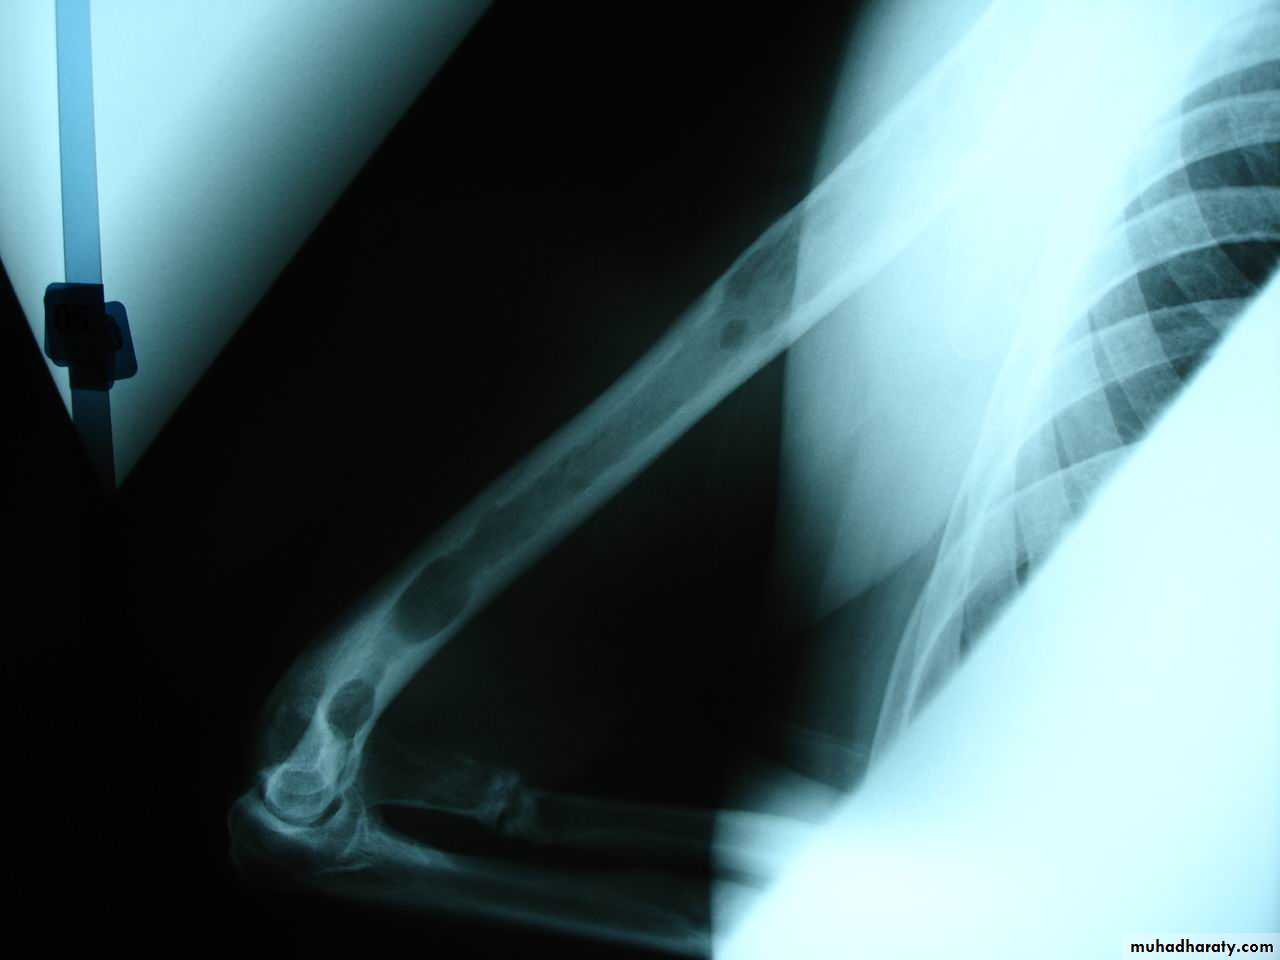

6Segmental fracture

The bone is fractured at more than one level